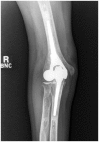

Modern elbow implants offer a high-performance articulation and the possibility of lateral column load sharing.